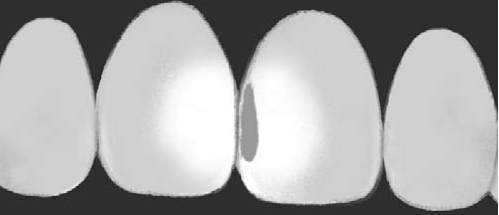

Transiluminación dentaria

La transiluminación antes de la aparición de la "tecnología led" solo era utilizada para la detección de caries proximal en los incisivos. En la actualidad dada la potencia lumínica de dichos dispositivos puede ser utilizada para la pesquisa de caries proximal y oclusal de la piezas dentales posteriores. Se utiliza una  lámpara led de luz día ( 5500 ºK)  con su fibra óptica, como se muestra en la fotografía inferior derecha.

La luz visible es enviada por medio de una  fibra óptica hasta la superficie del diente, dónde se propaga  a través del tejido hasta la superficie opuesta. El resultado  es una imagen que resulta de la distribución de la luz a en el interior d e la pieza dental. (1) Un proceso de caries en esmalte y dentina tiene la particularidad de un cuerpo opaco de reflejar la luz, en consecuencia la observación en la superficie opuesta generaría una imagen oscura.

Pero esté fenómeno que acabamos de explicar no es exclusivo de la caries, las hipoplasias (alteración del desarrollo del esmalte)  y las opacidades del esmalte debido a fluorosis y a otras sustancia químicas, como la tetraciclina y la metalosis de las amalgamas dentales,  pueden afectar la transmisión de la luz en el interior de la pieza dental, generando figuras ó imágenes opacas. (2,3). En general la transiluminación es un complemento ideal en el diagnóstico visual de caries de esmalte, (sensibilidad 96% y especificidad 74%) como de la dentina  (sensibilidad 89% y especificidad 92%) (4,5,6)

Para estandarizar el diagnóstico de caries por medio de la transiluminación, existen escalas que  clasifican  la severidad de la lesión en  proximal y oclusal:

Escala  de puntuación para transiluminación (ICDAS Combinado)

Sano No hay sombra o área manchada

Caries inicial Hay una sombra gris, que puede ser una línea  fina < 2 mm de la misma anchura, hasta una franja gris  < 4 mm.

Caries moderada  Hay una amplia  sombra (> 5mm) gris / naranja / marrón / azulada / negra cuando aplicamos luz.

Sano

¿Caries inicial ó moderada?

En apariencia cuando aplicamos luz, se mantiene el color gris. Pero cambiando el eje de luz, podemos ver el espesor de la sombra gris.

Sospechamos de una caries moderada por la amplia sombra gris.